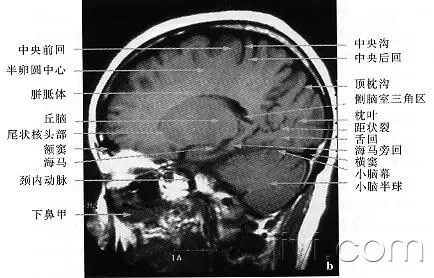

skC影像园XCTMR.com  1、蝶窦(Sphenoid sinus) 2、延髓 (Medulla oblongata) 3、小脑 (cerebellum) 绿色部分为颞叶(Temporal Lobe),浅红色部分为额叶(Frontal Lobe)skC影像园XCTMR.com skC影像园XCTMR.com skC影像园XCTMR.com  4、第四脑室(Fourth ventricle) 5、小脑中角(Middle cerebellar peduncle) 6、乙状窦(Sigmoid sinus) 7、颞骨及乳突气房 (Petrous temporal bone and mastoid air cells) 8、桥小脑角(Cerebellopontine angle) 9、脑桥 (Pons) 10、垂体窝(Pituitary fossa) 绿色部分为颞叶(Temporal Lobe),浅红色部分为额叶(Frontal Lobe)skC影像园XCTMR.com  skC影像园XCTMR.com 11、小脑蚓部(Cerebellar vermis) 12、基底动脉(Basilar artery) 13、桥前池 (Prepontine cistern) 14、鞍背 (Dorsum sellae) 15、侧脑室颞角(Temporal horn of lateral ventricle) 绿色部分为颞叶(Temporal Lobe),浅红色部分为额叶(Frontal Lobe)skC影像园XCTMR.com skC影像园XCTMR.com

16、环池 (Ambient cistern) 17、角间池 (Interpeduncular cistern) 18、大脑角 (Cerebral peduncle) 19、侧裂池 (Sylvian fissure) 绿色部分为颞叶(Temporal Lobe),浅红色部分为额叶(Frontal Lobe) skC影像园XCTMR.com | skC影像园XCTMR.com

20、小脑上池 (Third ventricle) 21、侧脑室前角 (Frontal horn of lateral ventricle) 21a、第三脑室 (Third ventricle) 绿色部分为颞叶(Temporal Lobe),浅红色部分为额叶(Frontal Lobe),黄色部分为枕叶(Occipital Lobe)skC影像园XCTMR.com | skC影像园XCTMR.com

22、尾状核头部 (Head of caudate nucleus) 23、岛叶 (Insular cortex) 24、外囊 (External capsule) 25、豆状核(Lentiform nucleus) 26、丘脑(Thalamus) 绿色部分为颞叶(Temporal Lobe),浅红色部分为额叶(Frontal Lobe),黄色部分为枕叶(Occipital Lobe)skC影像园XCTMR.com | skC影像园XCTMR.com

27、纵裂 (Interhemispheric fissure) 28、内囊前肢 (Anterior limb of internal capsule) 29、内囊膝部 (Genu of internal capsule) 30、内囊后肢(Posterior limb of internal capsule) 31、侧脑室三角区及脉络丛钙化(Trigone of lateral ventricle and calcified choroid plexus) 32、侧脑室枕角(Occipital horn of lateral ventricle) 绿色部分为颞叶(Temporal Lobe),浅红色部分为额叶(Frontal Lobe),黄色部分为枕叶(Occipital Lobe),褐色部分为顶叶(Parietal Lobe)skC影像园XCTMR.com | skC影像园XCTMR.com

33、侧脑室体部 (Body of lateral ventricle) 34、放射冠 (Corona radiata) 浅红色部分为额叶(Frontal Lobe),黄色